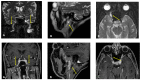

In the present study, through a case series, we highlighted the role of magnetic resonance (MR) in the identification and diagnosis of peripheral neuropathies. MR neurography allows the evaluation of the course of nerves through 2D and 3D STIR sequences with an isotropic voxel, whereas the relationship between nerves, vessels, osteo-ligamentous and muscular structures can be appraised with T1 sequences. Currently, DTI and tractography are mainly used for experimental purposes. MR neurography can be useful in detecting subtle nerve alterations, even before the onset of symptoms. However, despite being sensitive, MR neurography is not specific in detecting nerve injury and requires careful interpretation. For this reason, MR information should always be supported by instrumental clinical tests.